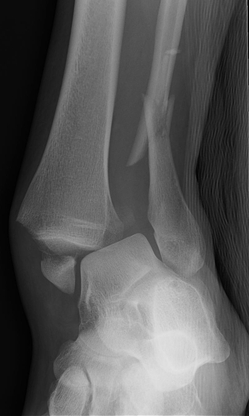

Your foot is made up of 26 small bones and more than 30 joints, all working together to provide balance and movement. A foot fracture occurs when one or more of these bones break due to trauma, stress, or overuse. A dislocation, on the other hand, happens when the bones in a joint move out of their natural alignment, usually following an accident or severe twisting injury.

Image

• X-rays – To identify broken or misaligned bones.